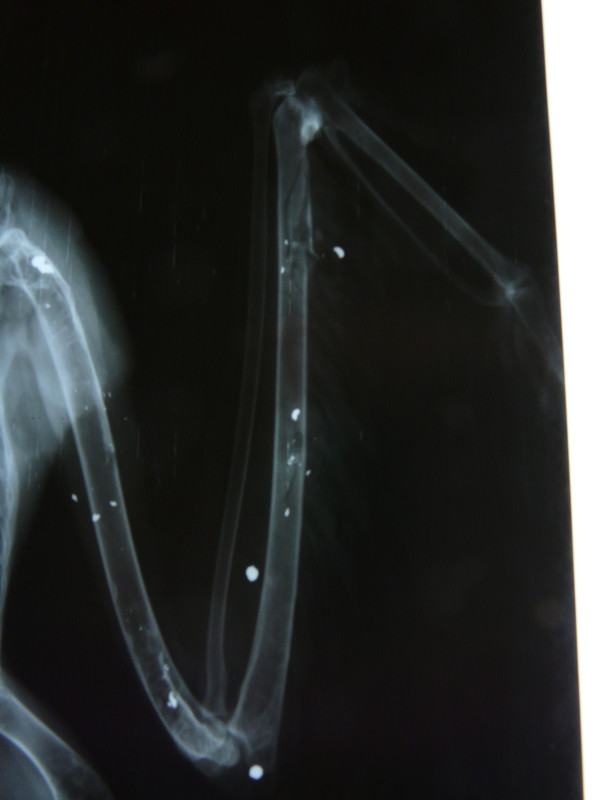

El primero, un ejemplar adulto de milano real ingresó muy aturdido pero con buena condición corporal, lo que nos hizo sospechar que la lesión era reciente. Un gran hematoma invadía toda el ala izquierda y encontramos algunos orificios pequeños en la piel. Se hizo una radiografía para ver el tipo de fractura (hallamos 2 fracturas en vez de una) y si era necesaria o viable la intervención quirúrgica, encontrándonos varios perdigones y numerosos fragmentos de metralla distribuidos por toda el ala y resto del cuerpo. Se aplicaron primeros auxilios y vendaje para inmovilizar la fractura que, afortunadamente, estaba alineada. Gracias a la fluidoterapia y cuidados intensivos el animal se estabilizó y a día de hoy se alimenta con normalidad y su comportamiento es el adecuado. Permanecerá con el vendaje puesto hasta la próxima semana, cuando haremos una radiografía de control para ver si hay formación de callo óseo, podemos retirar el vendaje y valorar el resultado tras este mes en la Enfermería. Se transferirá al departamento de Rehabilitación para empezar con fisioterapia y ver cuáles son las posibilidades reales de liberación de este ejemplar.